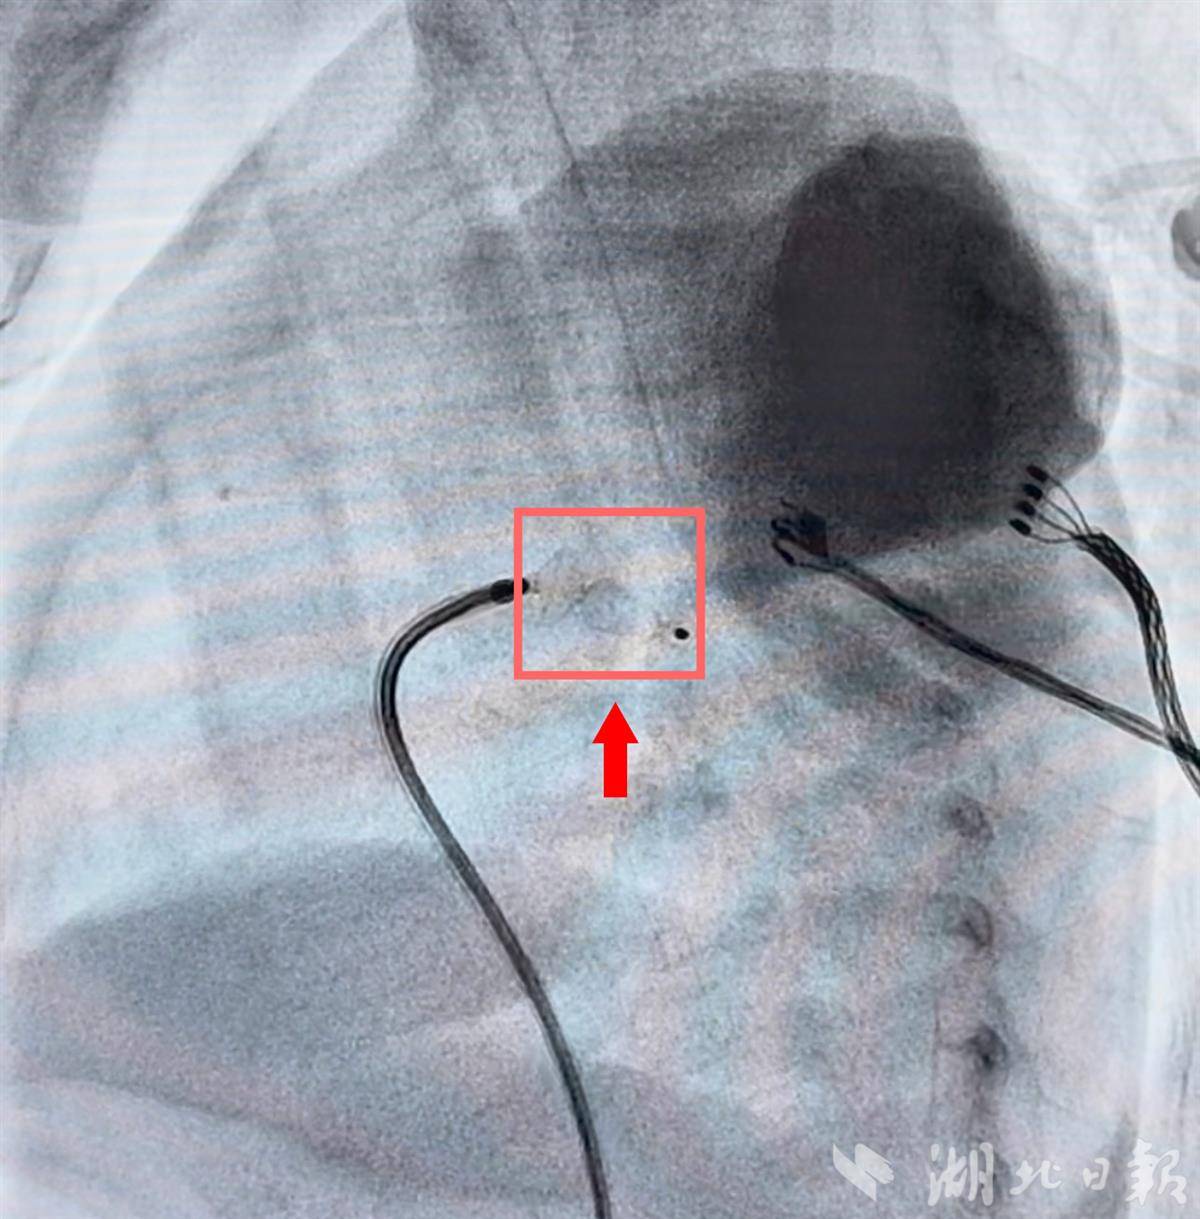

4月8日上午,手术正式开始。全身麻醉后,介入团队通过穿刺股静脉建立通道。李恒小心翼翼地将导丝和输送鞘穿过橙橙纤细的血管,精准定位到未闭合的动脉导管处。封堵器释放的一瞬间,造影显示:动脉导管分流立刻消失。

导丝成功将封堵器精准放置在未闭合的动脉导管处。(受访单位供图)

整台手术仅用了约40分钟,出血量极少。术后超声显示,封堵器位置稳定,心脏杂音消失。撤掉呼吸机后,橙橙的心功能明显改善。那个曾经奄奄一息的掌心宝宝,如今已能够自由地挥舞小手小脚。